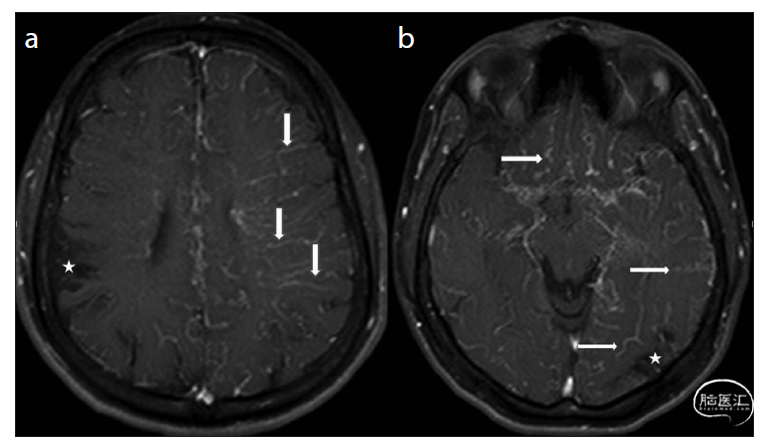

例二:

烟雾病病人,前循环闭塞,后循环向前代偿供血。可以看到双侧大脑后动脉通过皮层支向前、双侧大脑半球上外侧面代偿供血,还有后胼周动脉逆行向前、纵裂部位代偿供血。那么,血都供应到哪里了呢?正位上,由于前后重叠,看不到血流向前走了多少;侧位上,倒是能看到向前的分布,但是左右侧的代偿血管又重叠了。用DSA可能唯一的办法是进行三维旋转,或者4D DSA了。

T-ASL显示椎基底动脉的供血范围,向双侧颞叶的就是大脑后动脉皮层支的代偿;纵裂部位,就是后胼周动脉来的代偿血流。